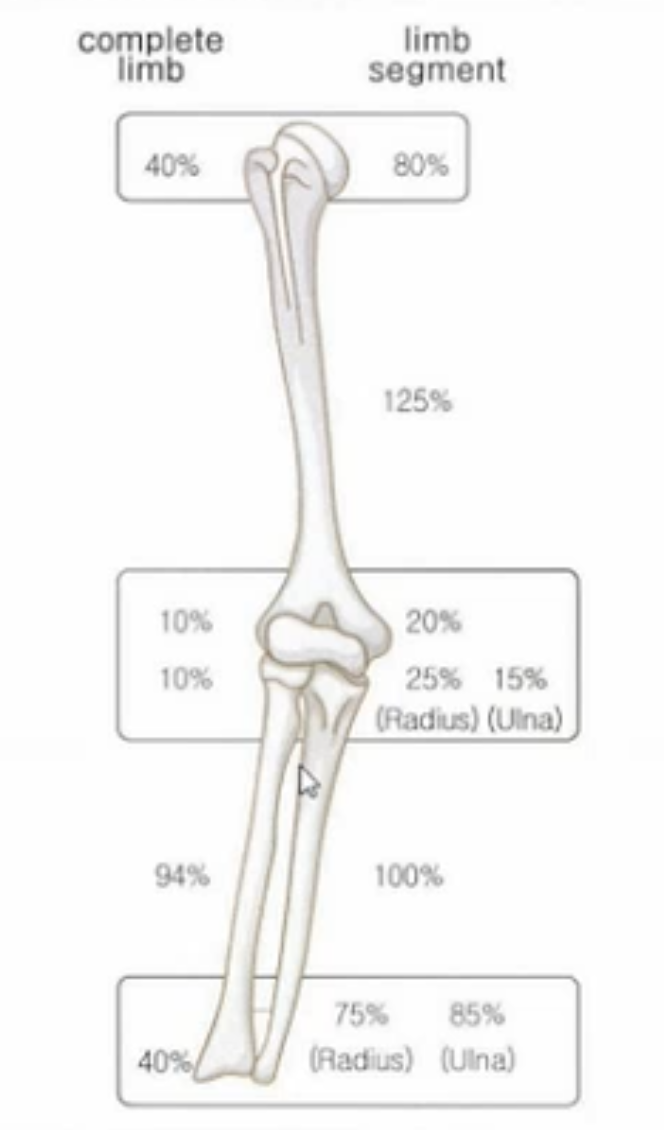

상완골의 경우 근위/원위 : 8:2 비율로

요골의 경우 근위/원위 2.5:7.5 비율로

척골의 경우 근위/원위 2:8 비율로 성장하게 됩니다.

(어깨관절이나, 완관절에서 길이성장이 많이 일어납니다.)

상지 전체로 보았을 때 총100% 기준 상완골 근위 40%/상완골 원위10%/요골 근위 10%/요골 원위 40% 로

상완골과 전완부의 골의 성장이 비등비등하다는 것을 알 수있습니다.